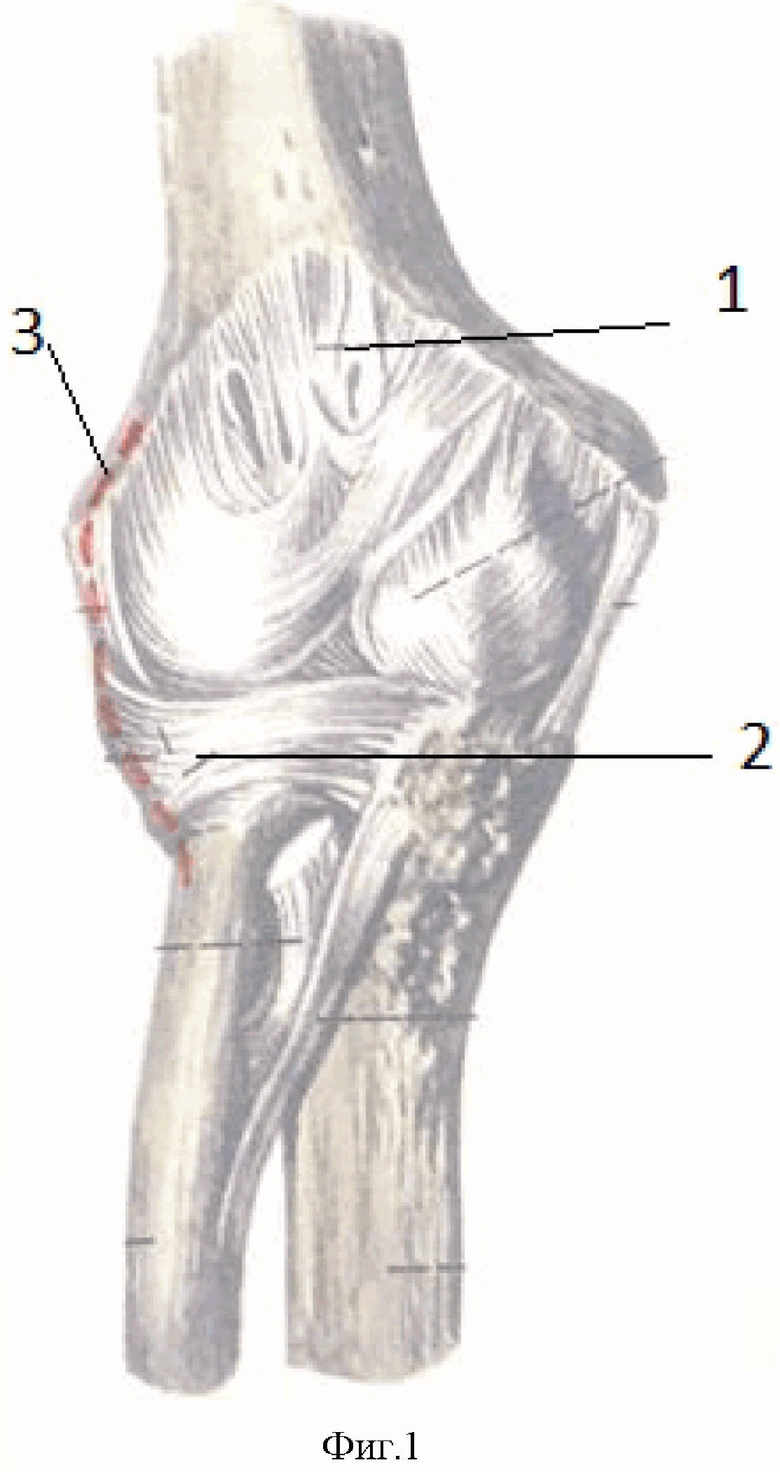

Радиоульнарный угол: строение и особенности лучевой кости